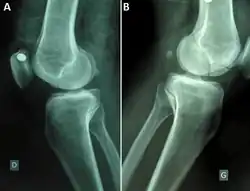

Medio-lateralradiographsof knees joint showing a bilateral Hoffa fracture of the medial femoral condyle and fracture suspicion of left tibia plateau. (A) right knee; (B) left knee.[1]

A Hoffa fracture is an intra-articular supracondylar distal femoral fracture, characterized by a fracture in the coronal plane.[1]